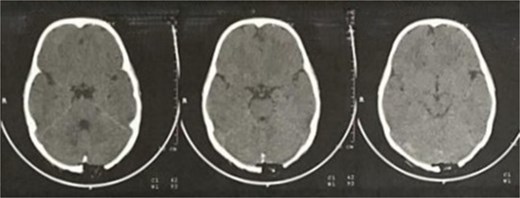

A 4-year-old, otherwise healthy male with no significant past medical history, family history of bone disorders, or prior trauma, presented with a progressively enlarging, painless occipital swelling noticed by his parents over a two-month period. The parents denied any associated symptoms, including fever, headache, vomiting, changes in behavior, or neurological deficits such as visual disturbances or gait abnormalities. There was no history of recent infections or constitutional symptoms. On physical examination, the child was afebrile and hemodynamically stable. A solitary, well-circumscribed, firm, non-mobile, and non-tender mass measuring 1.5 × 1.5 cm was palpated in the midline occipital region. The overlying skin was normal in color and temperature, with no erythema, ulceration, or punctum. No regional lymphadenopathy was detected. Neurological examination, including cranial nerve assessment, motor/sensory function, and reflexes, was unremarkable. Brain computed tomography (CT) with contrast revealed a 14 × 12 mm, well-defined, osteolytic, interosseous lesion in the occipital bone, exhibiting smooth sclerotic margins, cortical thinning, and no periosteal reaction or internal matrix mineralization, the lesion was confined to the diploic space, sparing the inner and outer cortical tables, with no intracranial extension or dural involvement (Figs 1 and 2). Magnetic resonance imaging (MRI) without contrast enhancement, T1-weighted imaging (T1WI) showed an extra-axial space-occupying mass, the mass is iso-intense and well-circumscribed in shape (Fig. 3).